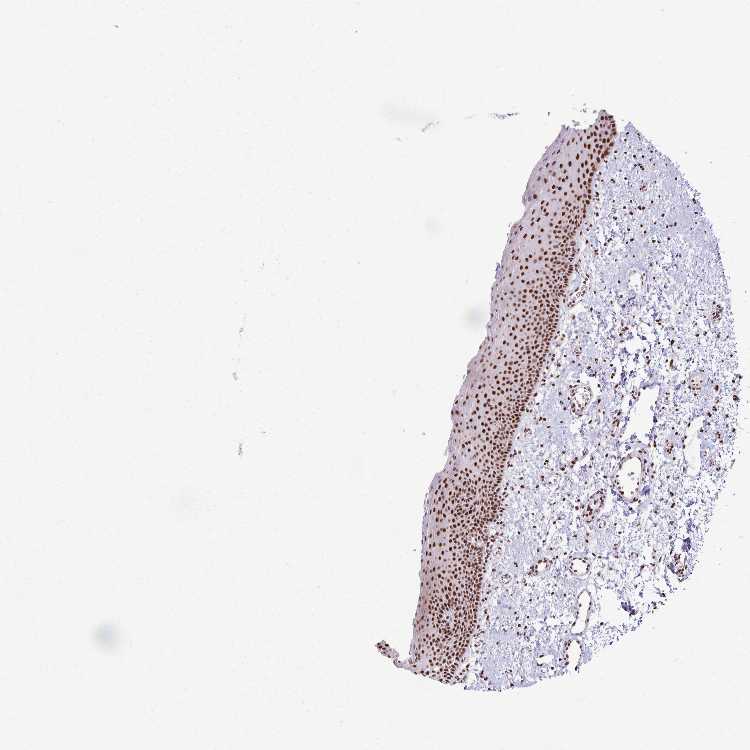

TISSUE PRIMARY DATA ORAL MUCOSA Show tissue menu

ORAL MUCOSA - Antibody stainingi

Antibody staining in the annotated cell types in the current human tissue is reported as not detected, low, medium, or high, based on conventional immunohistochemistry profiling in selected tissues. This score is based on the combination of the staining intensity and fraction of stained cells.

Each image is clickable and will lead to virtual microscopy that enables deeper exploration of all samples and also displays staining intensity scores, fraction scores and subcellular localization as well as patient and tissue information for each sample.

Antibody HPA047549Antibody HPA062226Antibody CAB004254

Squamous epithelial cells Not detectedHighHigh